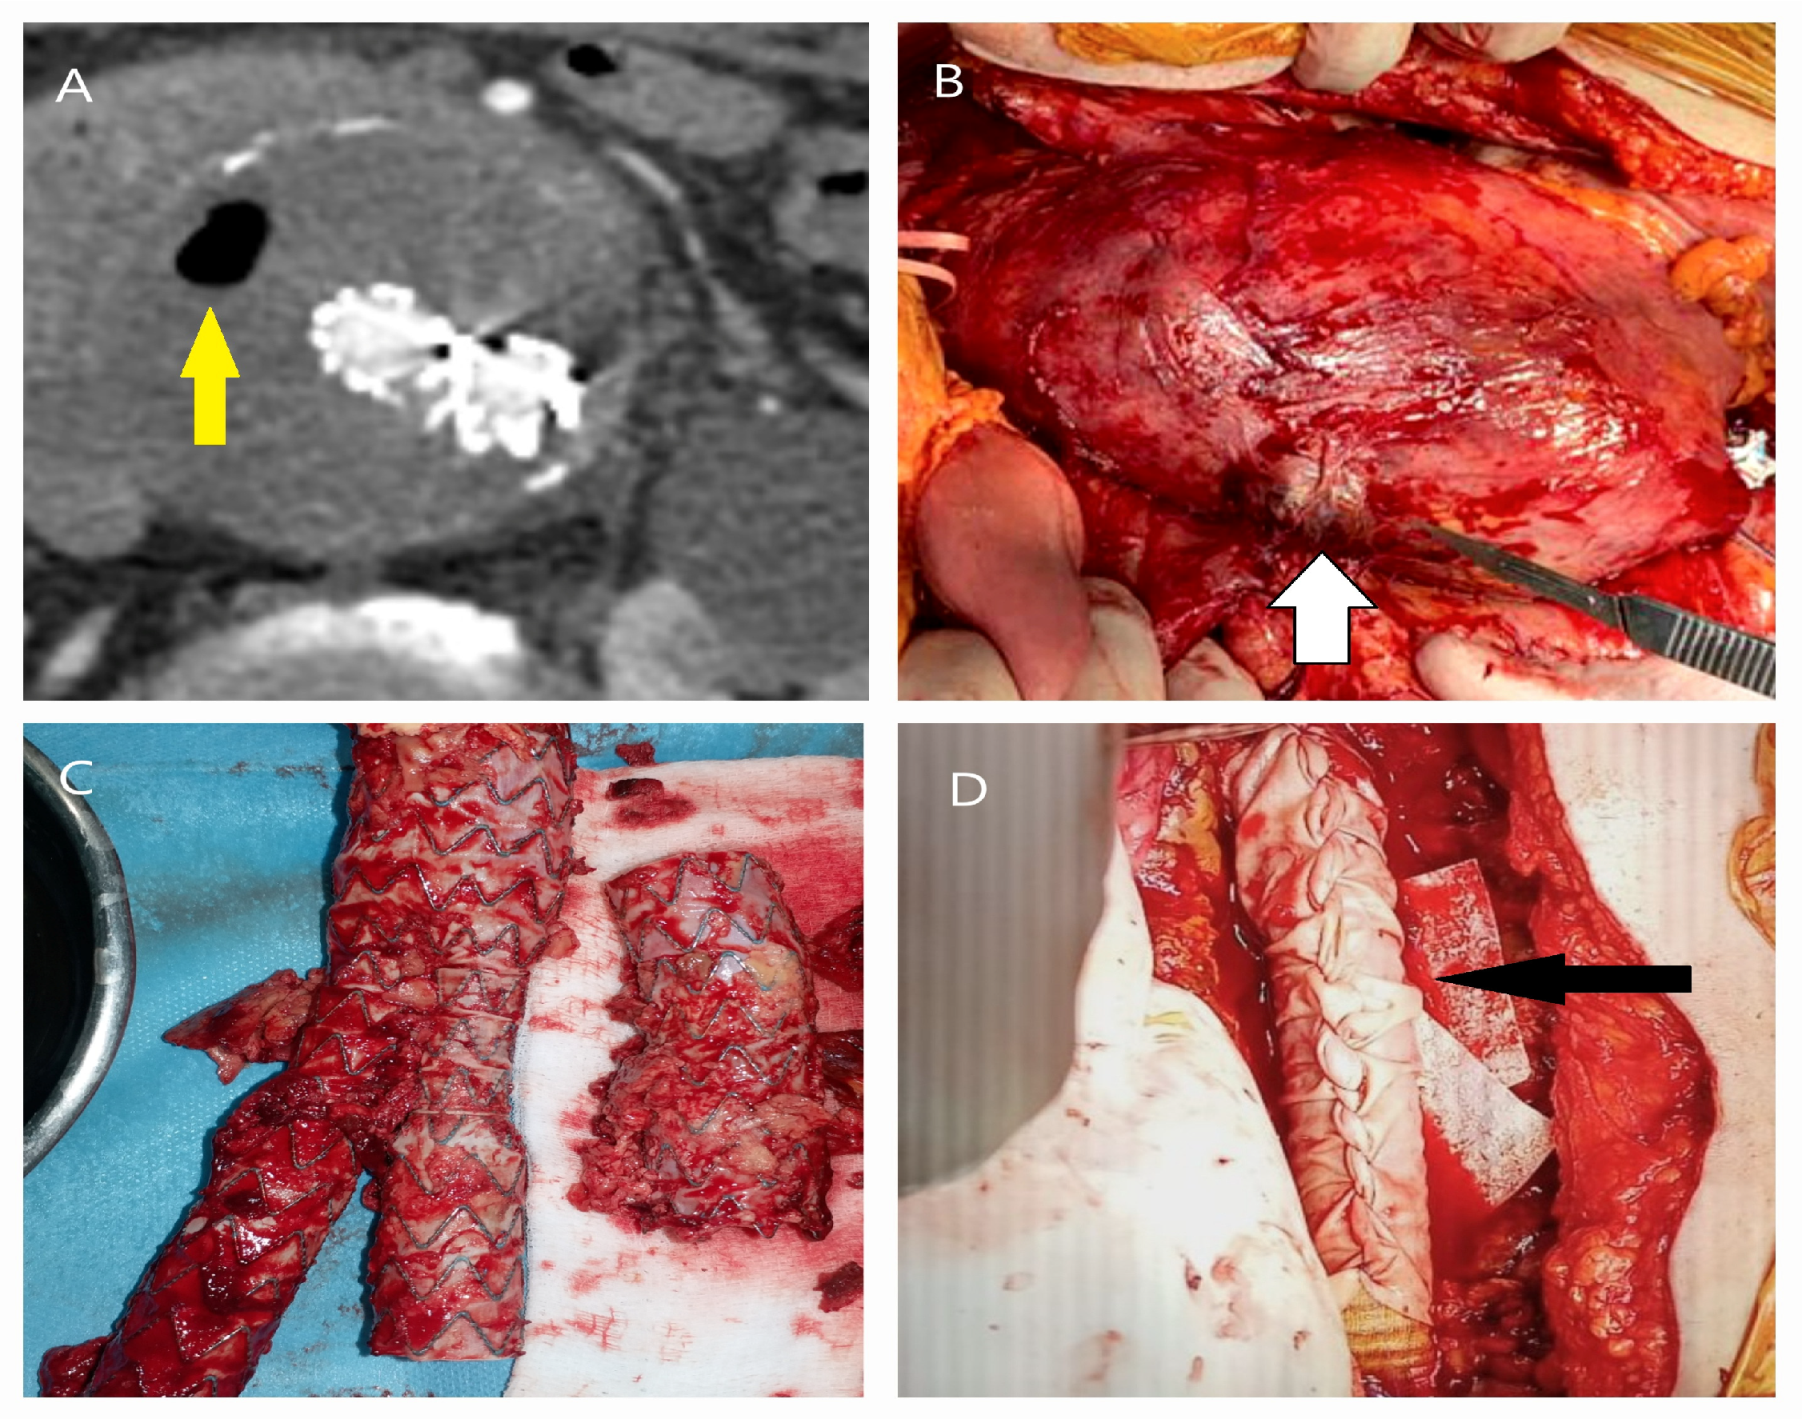

5.1. Failure of EVAR

5.2. Conversion to Open Surgery